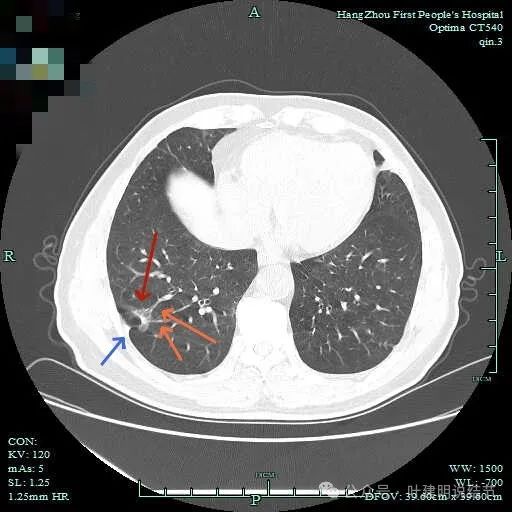

先看主病灶情况:

病灶出现,整体轮廓较清,胸膜略有牵拉。

密度不均匀,胸膜有轻微牵拉,边上有磨玻璃成分。

混合偏实性密度,瘤肺边界清,胸膜有牵拉。

表面不平,有小血管进入,整体轮廓与边界清。

明显胸膜牵拉以及血管进入,灶内密度不纯。

边缘毛糙有细毛刺,灶内密度不均;胸膜牵拉以及表面不平;黄色箭头示细支气管截断的样子。

血管征以及胸膜凹陷征。

轮廓与边界清,灶内有小空泡征。

多支血管进入,灶内密度不均。

胸膜牵拉,表面不平,血管进入并有异常增粗。

右下脊柱旁怎么也像有磨玻璃结节?但此处正常CT也是略显有慢性炎似的征象的,可这个病人明显结节状,还表面有细毛刺似的。